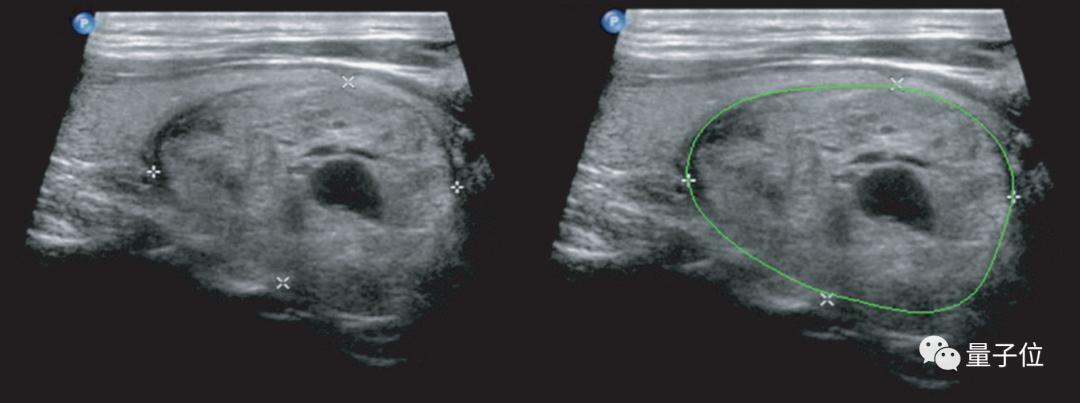

△ 使用深度学习进行的甲状腺结节检测和定性诊断(右)这种AI辅助诊断的准确度,当时就已经比中国甲等医院的放射科医生至少高出10%。